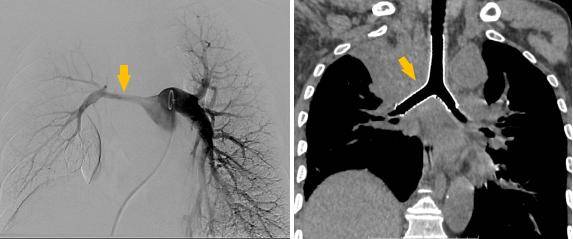

介入手术室里,一场无声的战役打响。麻醉科主任闫华凭借高超技术,成功为患者通气建立安全通路,为手术的实施奠定基石。介入科主任贺光辉带领团队细致操作,将一枚Y形气管支架在X线引导下输送至预定位置后精准释放,原本被肿瘤挤压得只剩一丝缝隙的气道被稳稳地撑开。紧接着一枚肺动脉覆膜支架置入到受压变窄的右肺动脉主干内并准确释放,再次造影,使得右肺动脉血流迅速得到改善。

手术过程